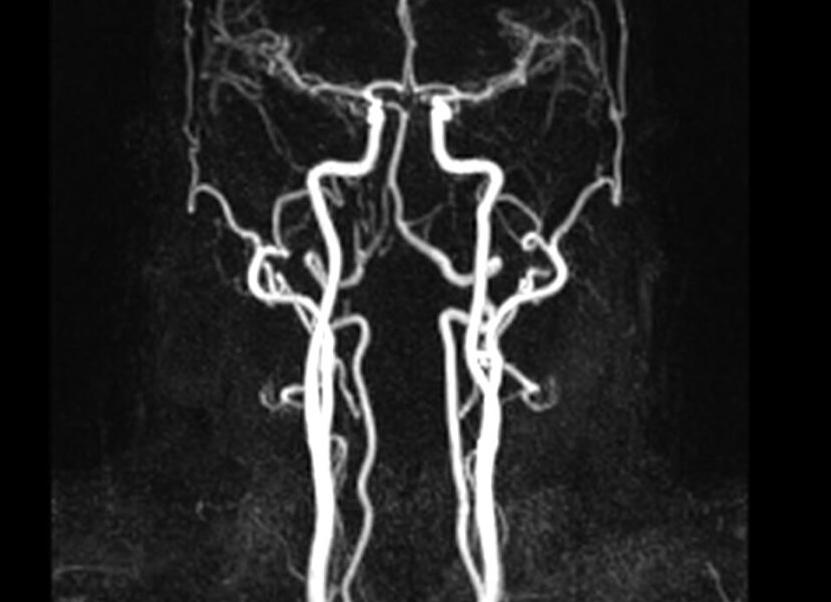

Наиболее распространенными на сегодняшний день методами с высокой точностью диагностики являются МРТ (магнитно-резонансная томография) и КТ (компьютерная томография).